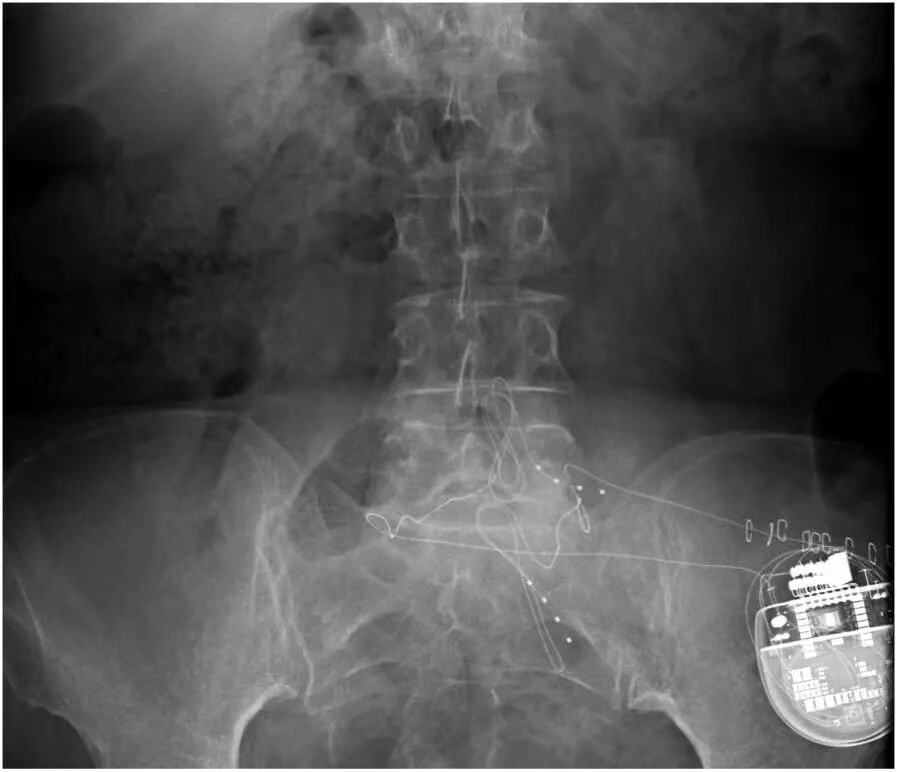

如果患者在试验期内对脊髓电刺激反应良好,且医生认为长期治疗可能对患者有益,那么就会考虑进行永久植入手术。在手术前,医生会与患者充分沟通,讨论植入的具体方式、预期的治疗效果以及可能存在的风险等。手术过程中,患者通常会接受全身麻醉或局部麻醉,医生会在透视引导下,将永久性电极精准地植入到硬膜外间隙,并确保电极与脊髓的位置关系合适。电极植入后,会将其与植入式脉冲发生器(IPG)相连,IPG 通常会被放置在患者的腹部或臀部皮下。手术后,医生会对 IPG 进行编程,根据患者的个体情况设置合适的刺激参数,以达到最佳的治疗效果。